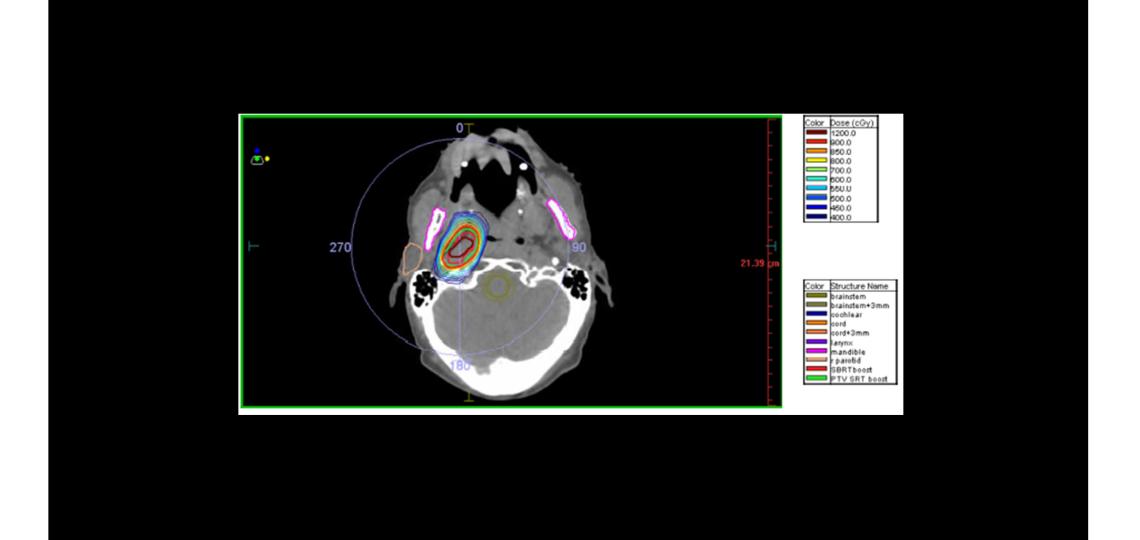

Stereotactic Radiotherapy for Head and Neck Cancer

Stereotactic body radiotherapy (SBRT) also known as stereotactic ablative radiotherapy (SABR) is a precise, painless, non-invasive radiation treatment that utilizes very accurately targeted, large “killing” doses of radiation. This non-invasive treatment has proven to be an effective alternative to surgery or conventional radiation for treating many small tumors and other select medical disorders. At the Baylor St. Luke’s Kirby Glen Radiation and CyberKnife facility, the CyberKnife system is utilized to deliver SBRT/SABR. It is the world’s first and only radiosurgery system designed to treat tumors anywhere in the body with sub-millimeter accuracy. Baylor St. Luke’s Radiation Therapy and CyberKnife Center is the only public center in Houston to offer CyberKnife radiosurgery.

Using image guidance technology and computer-controlled robotics, the CyberKnife system is designed to continually track, detect and correct for tumor and patient movement throughout the treatment. Because of its extreme precision, the CyberKnife system does not require invasive head or body frames to stabilize patient movement, vastly increasing the system’s flexibility. The CyberKnife procedure requires no anesthesia, can be performed on an outpatient basis and allows for the treatment of patients that otherwise would not have been treated with radiation or who may not have been good candidates for surgery. In addition, the CyberKnife procedure avoids many of the potential risks and complications that are associated with other treatment options.